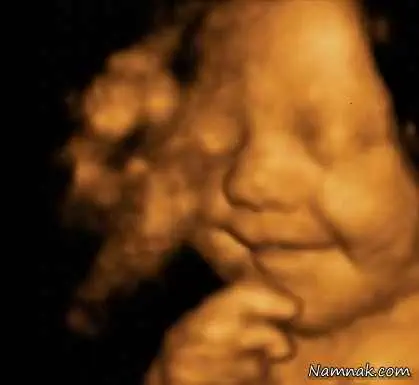

تمامی تصاویری که از سونوگرافی هفته 31 به بعد دوران بارداری مادر لئو موجود است به نوعی این ایده را تأیید می کند، زیرا به طرز شگفت انگیزی جنین در رحم مادرش همواره لبخندی به لب داشته است

تصویر سونوگرافی 31 هفتگی لئو، در حال لبخند زدن

این اولین تصویر ثبت شده از نوزادی است که حتی پیش از ورودش به این دنیا به تمامی آن چیزی که انتظارش را می کشید لبخند می زد.